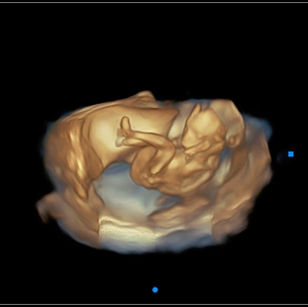

18 Weeks Pregnant

Size: ~5.5 inches (14 cm), the size of a Bell Pepper!

Development Highlights:

Baby can hear sounds and may respond.

Vernix caseosa begins forming to protect skin.

Joints more flexible; baby can bend arms and legs.

Baby may start thumb sucking.